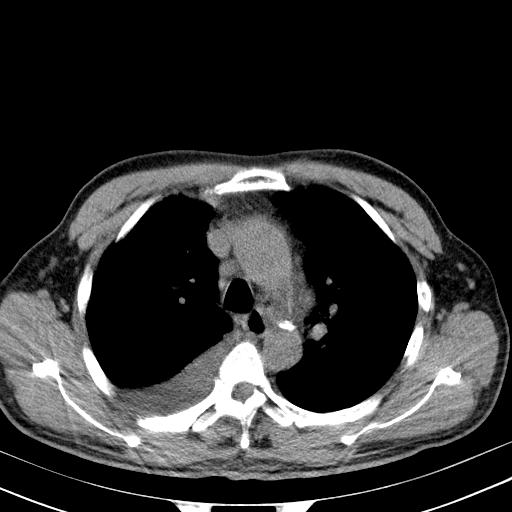

以下是引用zjzjr在2010-3-21 17:39:00的发言:[br]右下中心型肺癌并阻塞性肺炎/不张,纵膈淋巴结肿大,右侧大量胸腔积液,左侧少量胸腔积液

以下是引用zxl51642在2010-3-21 17:06:00的发言:[br]右下中心型肺癌并阻塞性肺炎/不张,纵膈淋巴结肿大,右侧大量胸腔积液,左侧少量胸腔积液,少量腹水。建议纤维支气管镜进一步检查。